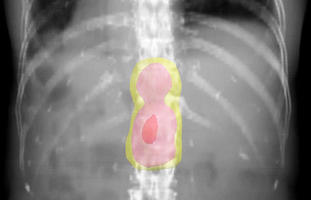

転移した部位に、5日間に計5回の放射線治療をします。黄色から赤色の部分にかけて=図2=強く放射線が当たっています。放射線治療の2年後には、骨の再石灰化が見られます=図3=(赤い矢印部分に新たな石灰化)。それと同時に痛みが減り、鎮痛薬も減らすことができます。効果は半年ぐらいですが、亡くなるまで、痛みがぶり返さなかった患者もたくさんいます。ほとんどが通院で治療ができ、1回10分ぐらいで済みます。治療日数は、病院までの距離や交通手段、サポートしてくれる人の有無などを考えて、1~10回となります。